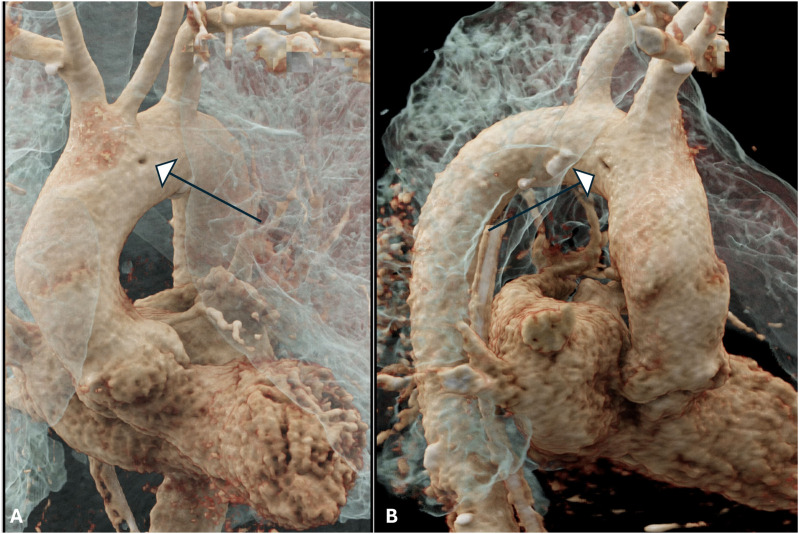

背景:随着越来越多地使用成像技术诊断人体病理,越来越多新的主动脉异常被发现。主动脉内索就是这样一种异常,需要与夹层的内膜瓣区分开来,以避免大手术或长期监护。本研究的目的是利用容积渲染重新格式化技术,提出主动脉内索在成像上的独特特征,并确定已发表文献中的类似发现,从而确定 "小酒窝 "征的作用:方法:回顾本院的成像(2 例)和已发表的文献(6 例),以确定主动脉容积渲染成像中是否存在诊断征象:结果:"酒窝征 "是主动脉内索特有的征象,在之前发表的 6 篇文献中,有 4 篇的图像中出现了这一征象。有两篇文章没有使用容积渲染。包括我们的病例在内,8 个病例中有 6 个出现了 "酒窝征"。出现 "酒窝 "征的原因是脐带拴系在主动脉壁上,导致主动脉壁向内脐化发展:结论:"酒窝 "征在容积和/或电影渲染中很容易观察到,是诊断主动脉内脐带的有用征象,有助于将其与内膜瓣区分开来。

BackgroundWith increasing use of imaging to diagnose human pathology, newer aortic anomalies are being identified. An intra-aortic cord is one such abnormality, which requires differentiating from an intimal flap of dissection, to avoid major surgery or prolonged surveillance. The aim of this study was to bring forth a unique feature of the intra-aortic cord on imaging, using volume rendering reformatting and identify similar findings in published literature and hence establish the role of the 'Dimple' sign.MethodsReview of both our institutional imaging (2 cases) as well as the published literature (6 cases), to identify presence of a diagnostic sign that is seen on volume rendered imaging of aorta.ResultsThe 'Dimple sign' is unique to the intra-aortic cord and is noted on the images of 4 out of 6 prior publications. Two publications did not use volume rendering. Including our cases, the Dimple' sign is seen in 6 out of 8 cases. The Dimple sign arises due to tethering of the cord to the aortic wall leading to umbilication of the aortic wall inwards.ConclusionsThe Dimple sign can be very easily noted on volume and/or cinematic rendering and is a useful sign to diagnose an intra-aortic cord and help differentiate it from an intimal flap.